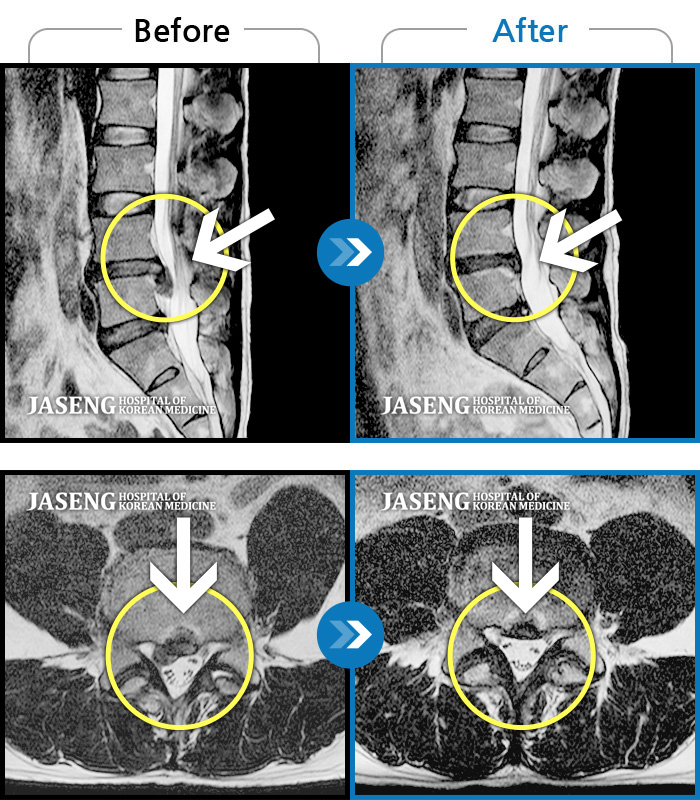

허리디스크

인천 · 강아현 원장

좌측 허리 통증 및 골반 통증이 심하여 걷는 것도 힘든 상태로 내원하셨습니다.

촬영시기

2024.05.08 ~ 2025.11.12

2025.11.14